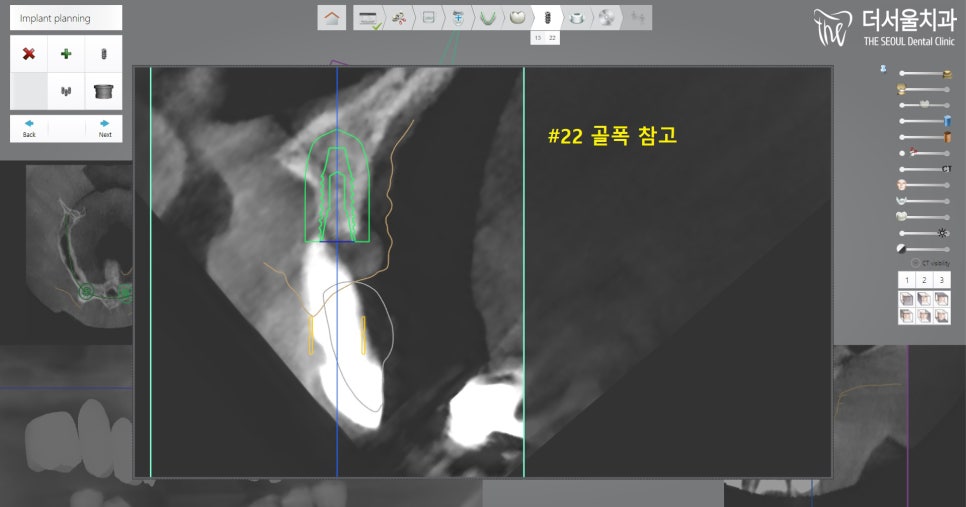

3. 수술 계획 수립 과정

먼저 환자분께 부담이 가지 않게끔

최소 절개를 통하여 진행할 수 있는

가이드 제작에 들어갔습니다.

원래 13번은 발치 계획에 없었으나,

상태가 그렇게 좋지 않았기에

제거하기로 결정을 내렸습니다.

그래서 13번과 22번 위치에 픽스처를 심고,

둘을 지대치로 이용하여

브릿지를 연결시켜 사용하기로 합니다.

아래에 검사를 하는 부분에서

보여지는 것처럼

뼈 상태가 너무 좋지 않기에,

추가적으로 뼈이식을 하기로 합니다.

좀 더 확대해서 보면,

이렇게 픽스처가 골폭을 벗어나있죠?

이러면 제대로 고정되지 않습니다.

결국, 실패로 이어지기에

뼈이식을 해야 되었죠.